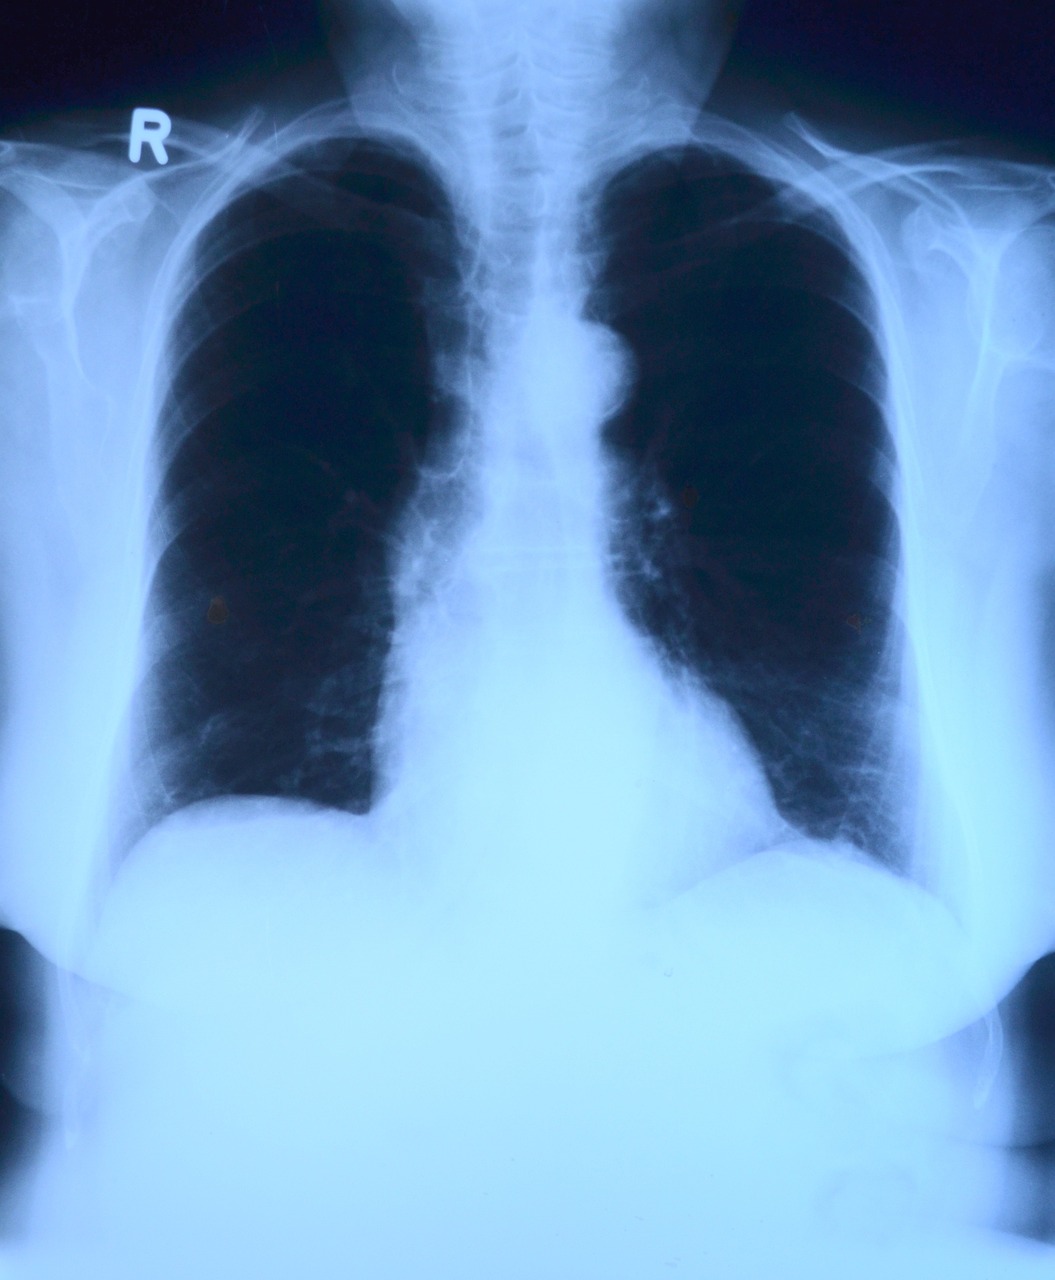

결핵균에 의해 유발되는 결핵은 주로 폐에 영향을 미치지만 다른 장기에 잠재적인 영향을 미치는 전염병입니다. 종종 기침이나 재채기를 통해 공기 중으로 전염되는 것은 결핵의 확산을 촉진합니다. 초기 증상은 경미할 수 있어 조기 발견이 어렵습니다. 그러나 시기적절한 식별과 치료가 진행을 중단시키는 데 가장 중요합니다. 결핵의 복잡성은 덜 심각한 상태를 모방하여 진단을 지연시키는 능력에 있습니다. 일단 감염되면, 사람들은 자신도 모르게 그 병을 퍼뜨릴 수 있으며, 결핵의 미묘한 징후를 인식하는 것의 중요성을 강조합니다. 결핵의 찾기 어려운 특성을 인정하면, 우리는 종합 검진과 공중 보건 교육을 우선시하여 보다 신속한 개입을 가능하게 합니다.